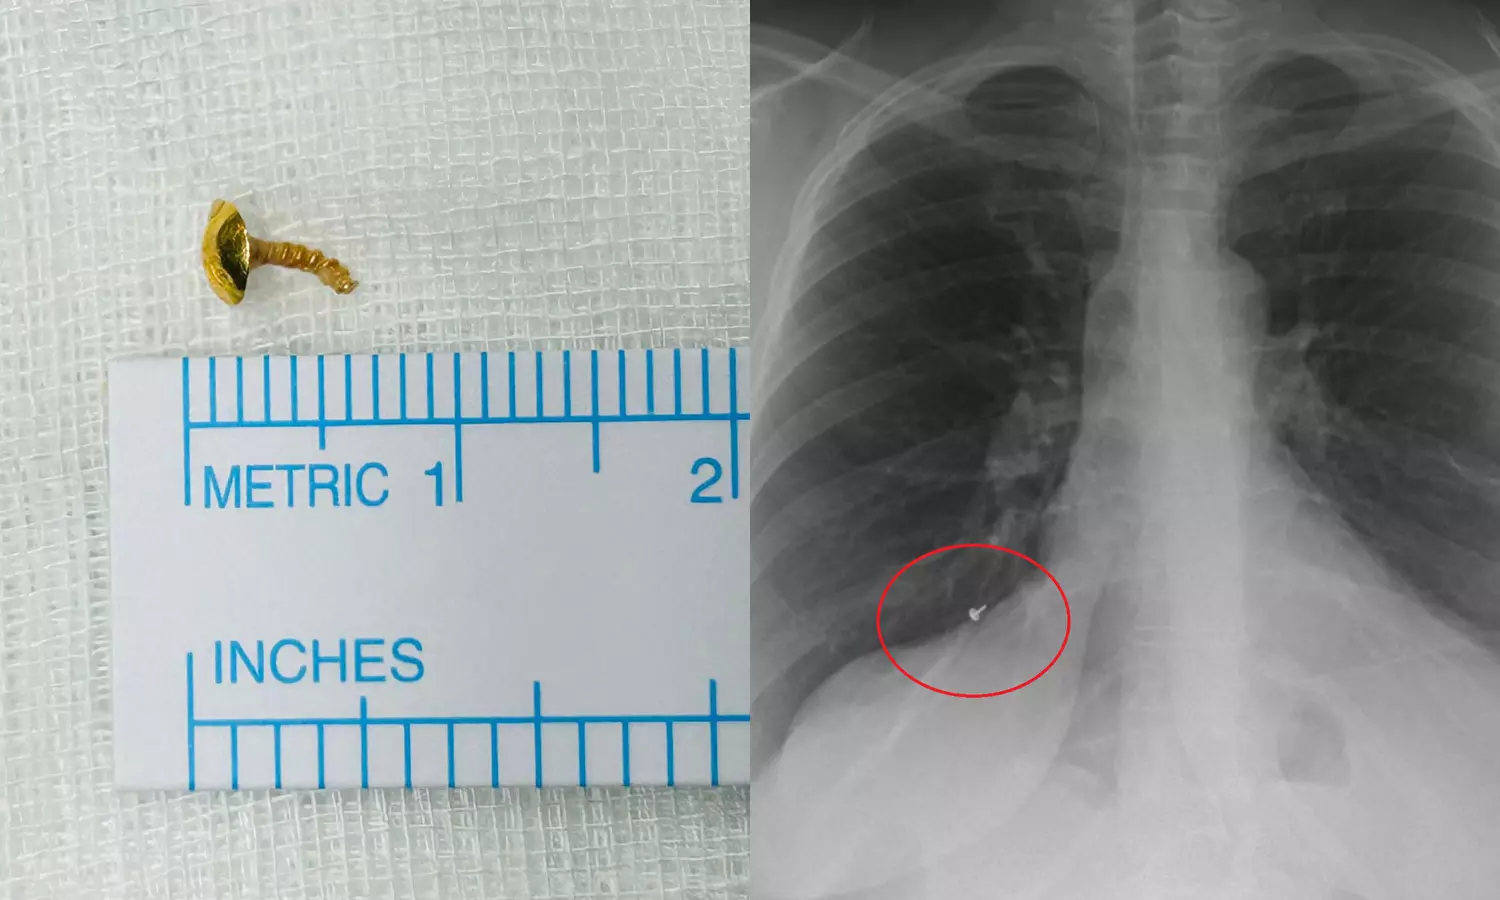

12 വർഷം മുമ്പ് കാണാതായ മൂക്കുത്തിയുടെ ഭാഗം വീട്ടമ്മയുടെ ശ്വാസകോശത്തിൽ നിന്ന് കണ്ടെടുത്തു

കൊച്ചി: വീട്ടമ്മയുടെ ശ്വാസകോശത്തിൽ നിന്ന് ഒരു സെന്റിമീറ്റർ നീളത്തിലുള്ള മൂക്കുത്തിയുടെ ഭാഗം പുറത്തെടുത്തു. കൊല്ലം ശാസ്താംകോട്ട സ്വദേശിനിയായ 44കാരിയുടെ ശ്വാസകോശത്തിൽ നിന്നാണ് മൂക്കുത്തിയുടെ ചങ്കിരി പുറത്തെടുത്തത്. കൊച്ചി അമൃത ആശുപത്രിയിലെ ഡോക്ടർമാരാണ് ശസ്ത്രക്രിയ കൂടാതെ മൂക്കുത്തിയുടെ ഭാഗം പുറത്തെടുത്തത്.

12 വർഷങ്ങൾക്കു മുമ്പാണ് വീട്ടമ്മയ്ക്ക് മൂക്കുത്തിയുടെ ചങ്കിരി നഷ്ടമായത്. മൂക്കുത്തിയുടെ പ്രധാനഭാഗം വീട്ടിൽ നിന്ന് കിട്ടിയെങ്കിലും പിറകിലെ പിരി കിട്ടിയില്ല. ഇതിനായി വീട്ടിൽ ഏറെ തെരച്ചിൽ നടത്തിയെങ്കിലും കിട്ടാതായതോടെ വീടിന് പുറത്തെവിടെയെങ്കിലും ഇത് വീണ് പോയിരിക്കുമെന്ന് കരുതിയിരിക്കുകയായിരുന്നു വീട്ടമ്മ.

ഒടുവിൽ കഴിഞ്ഞയാഴ്ച കൊല്ലത്തെ സ്വകാര്യ ആശുപത്രിയിൽ ശസ്ത്രക്രിയയ്ക്ക് വിധേയയായപ്പോൾ നടത്തിയ സ്‌കാനിങ്ങിലാണ് ശ്വാസകോശത്തിൽ എന്തോ തറഞ്ഞിരിക്കുന്നതായി കണ്ടെത്തിയത്. തുടർന്ന് വിദഗ്ധ ചികിത്സയ്ക്കായി കൊച്ചിയിലെ ആശുപത്രിയിലെത്തുകയായിരുന്നു. ഡോ.ടിങ്കു ജോസഫിന്റെ നേതൃത്വത്തിൽ നടത്തിയ പരിശോധനയിൽ ഇത് മൂക്കുത്തിയുടെ ഭാഗമാണെന്ന് കണ്ടെത്തുകയും റിജിഡ് ബ്രോങ്കോസ്‌കോപിയിലൂടെ പുറത്തെടുക്കുകയുമായിരുന്നു.

ഒരു ദിവസത്തെ വിശ്രമത്തിനു ശേഷം യുവതി കഴിഞ്ഞദിവസം ആശുപത്രി വിട്ടു. ഉറക്കത്തിനിടെ ഊരിപ്പോയ മൂക്കുത്തിയുടെ ഭാഗം മൂക്കിനുള്ളിലൂടെ വായിലെത്തി ശ്വാസകോശത്തിലേക്ക് പോയതാവാമെന്നാണ് കരുതുന്നത്. ഈ കാലയളവിൽ ശ്വാസതടസവും മറ്റു ബുദ്ധിമുട്ടുകളും നേരിട്ടതിനെ തുടർന്ന് വീട്ടമ്മ ആസ്തമയ്ക്ക് ചികിത്സ തേടുകയും ചെയ്തിരുന്നു.